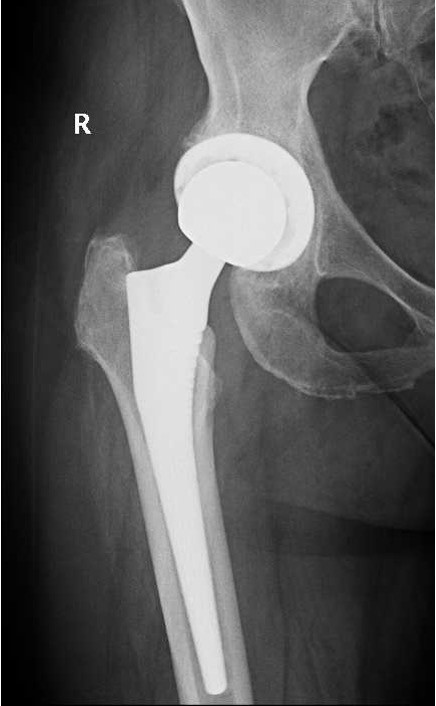

Είναι η επέμβαση με την οποία ένα προσβεβλημένο-εκφυλισμένο ισχίο αντικαθίσταται από μία πρόθεση.

Χρησιμοποιώντας σύγχρονα υλικά αντικαθίστανται η κοτύλη και η μηριαία κεφαλή.